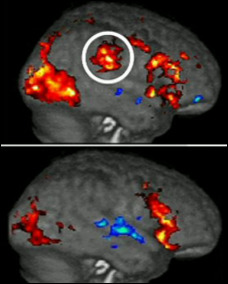

The researchers have discovered this by showing pictures of various injuries to volunteers while scanning their brains. This is a scan of the brains of two different subjects who are looking at pictures of injured people. The coloured areas show brain activity.

Both are having an emotional response but notice the difference. The red area we've ringed in the top scan is activity in the brain's pain centre. It's not in the bottom scan. The subject in the top scan is having an emotional response and feeling pain too.